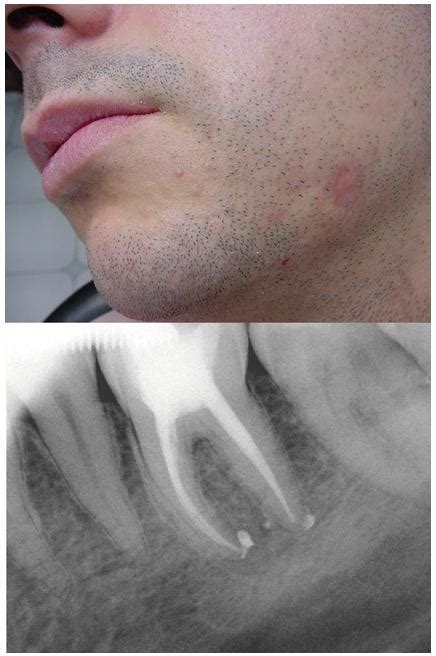

El diagnóstico de una fístula dental requiere una evaluación exhaustiva por parte de un dentista. Durante el examen, el dentista examinará detenidamente su boca y buscará hinchazón, enrojecimiento, lesiones y otras anomalías en las encías. A continuación, realiza una prueba de frío para comprobar si la raíz o el nervio del diente siguen siendo plenamente funcionales o ya han muerto. Si el diente está sano, al paciente le resultará desagradable el frío y reaccionará en consecuencia. A continuación, se realiza una radiografía de la mandíbula para que el dentista pueda reconocer si los huesos maxilares ya están afectados por la inflamación y dónde se encuentra exactamente el foco inflamatorio.